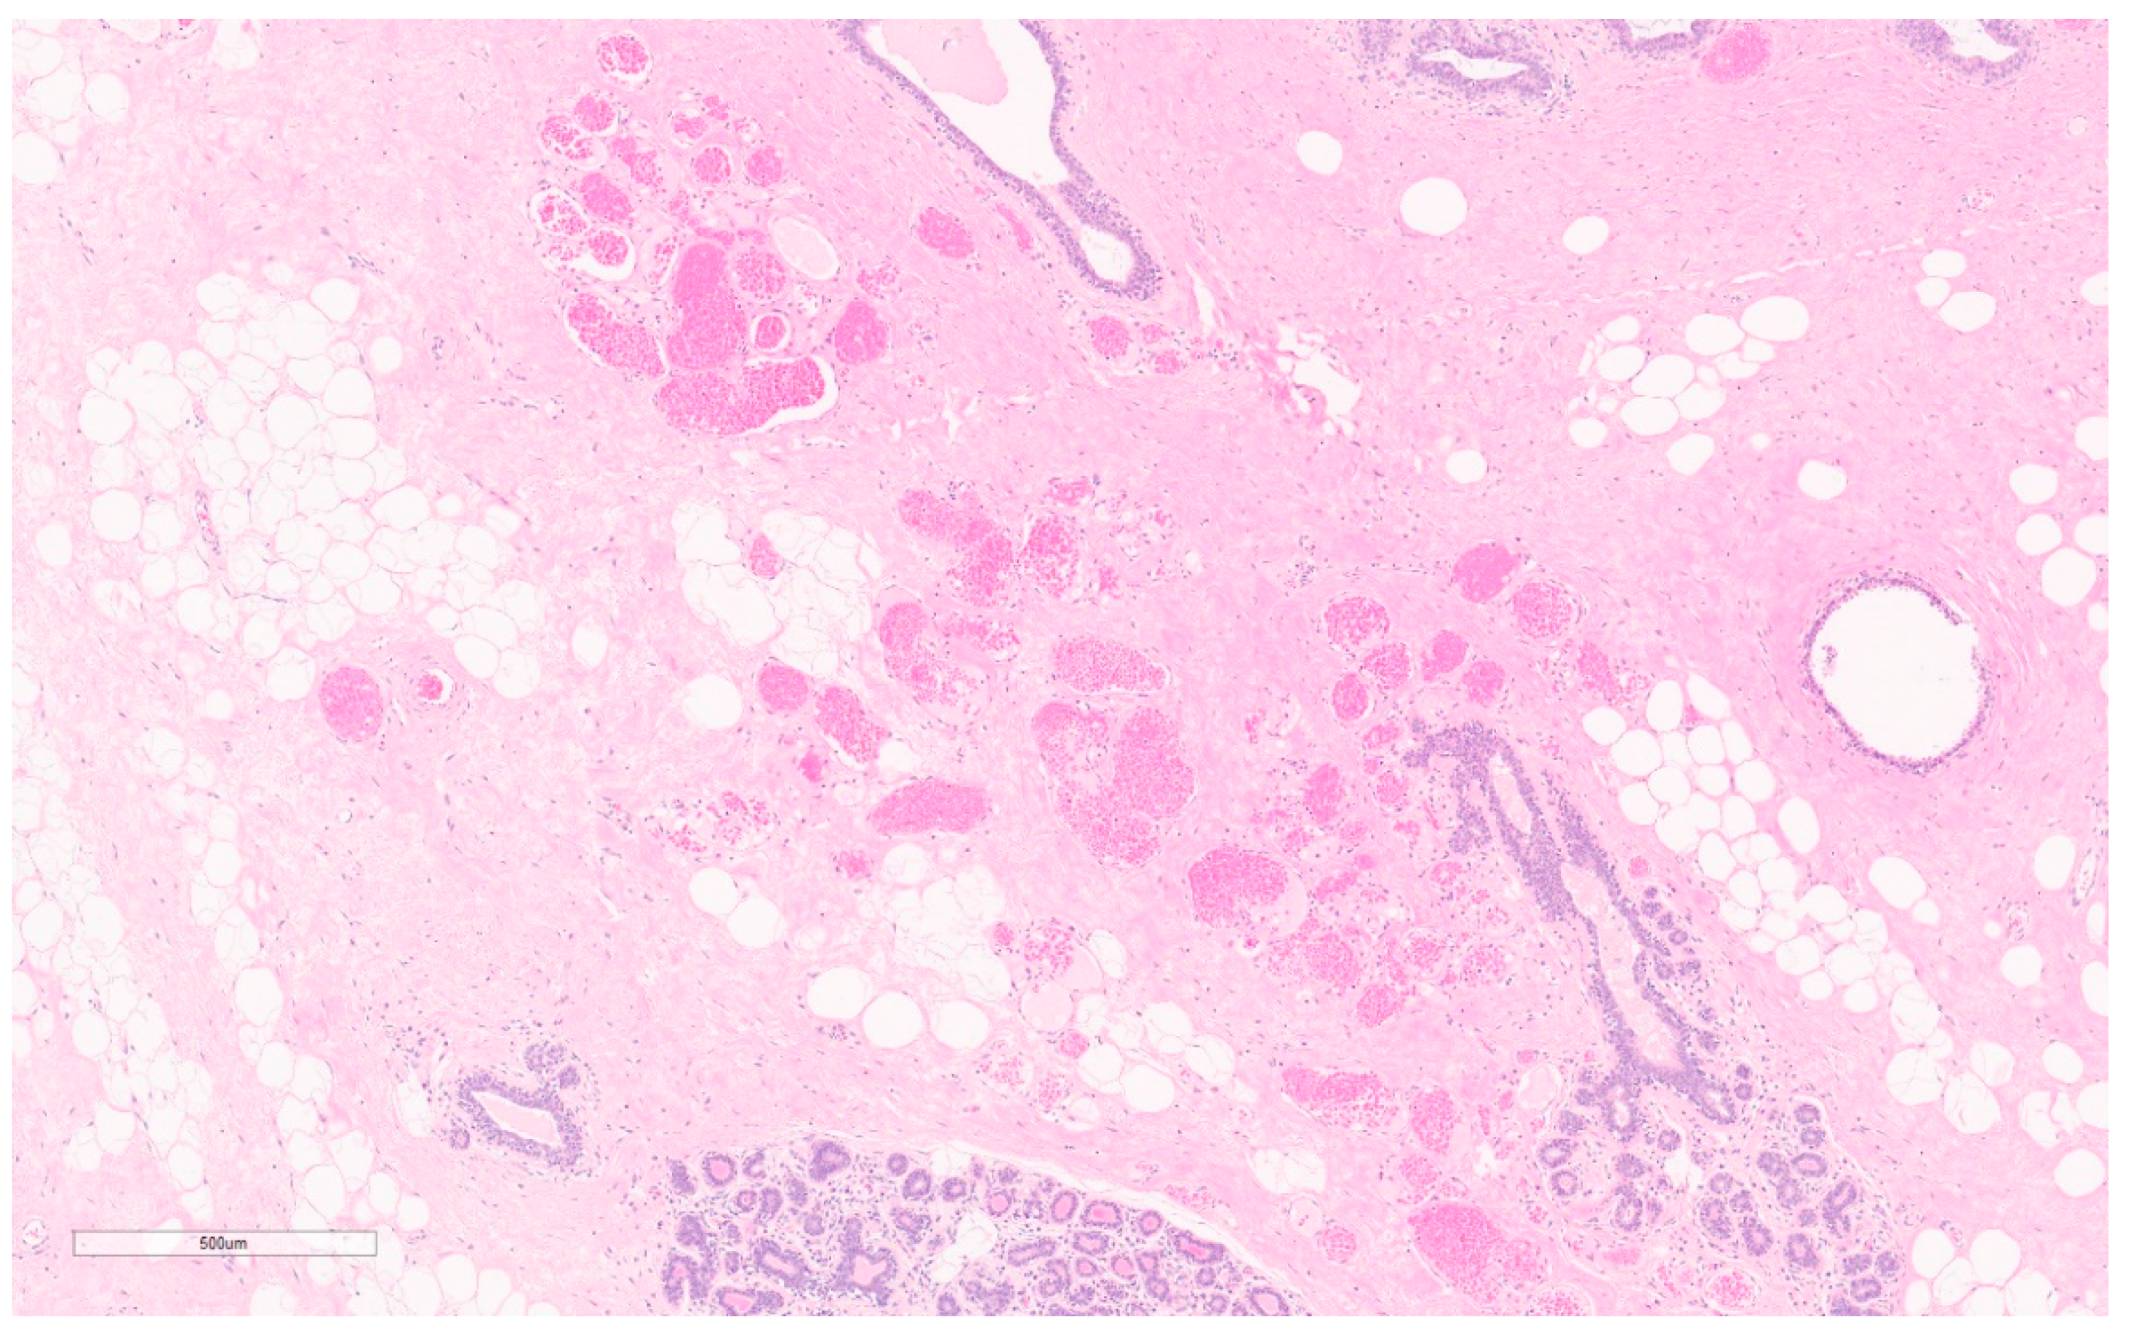

5.2. Angiolipoma

Summary of Updates